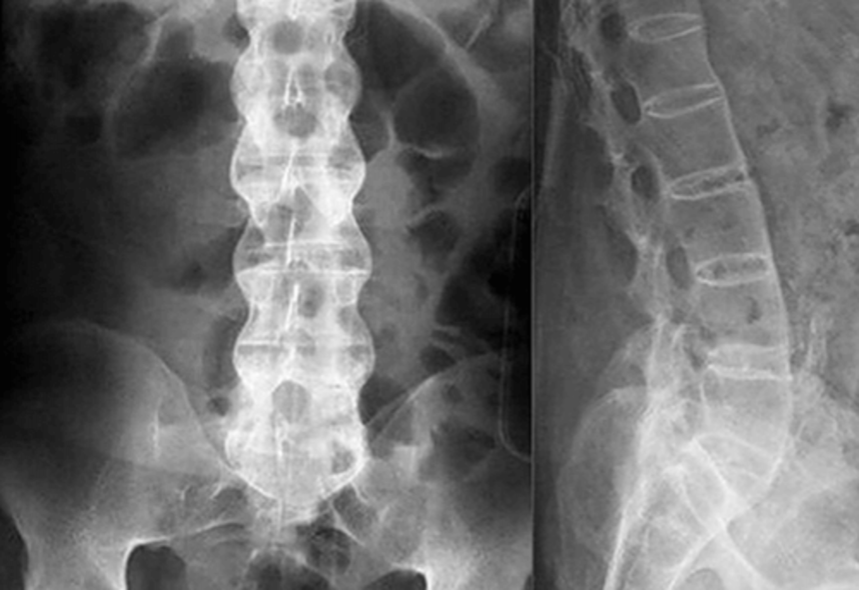

Рентген поясницы: анатомические особенности и медицинские исследования